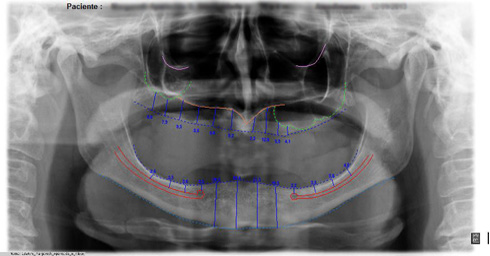

Também chamada de ortopantomográfica. Permite em uma única tomada, a visualização das estruturas do complexo maxilo-facial , conferindo portanto sua utilidade em todas as especialidades. Devido ao posicionamento do paciente (afastado do filme) a imagem não possui a mesma riqueza de detalhes finos como na periapical, porém vantagens como ampla cobertura da área examinada, a projeção das estruturas anatômicas com reduzida superposição , além da baixa dose de radiação, são justificativa de sua crescente aceitação.

Com o auxílio de um software específico as estruturas anatômicas são evidenciadas e realizamos medidas lineares já corrigindo o valor de ampliação da imagem (específico para cada tipo de aparelho e fabricante).